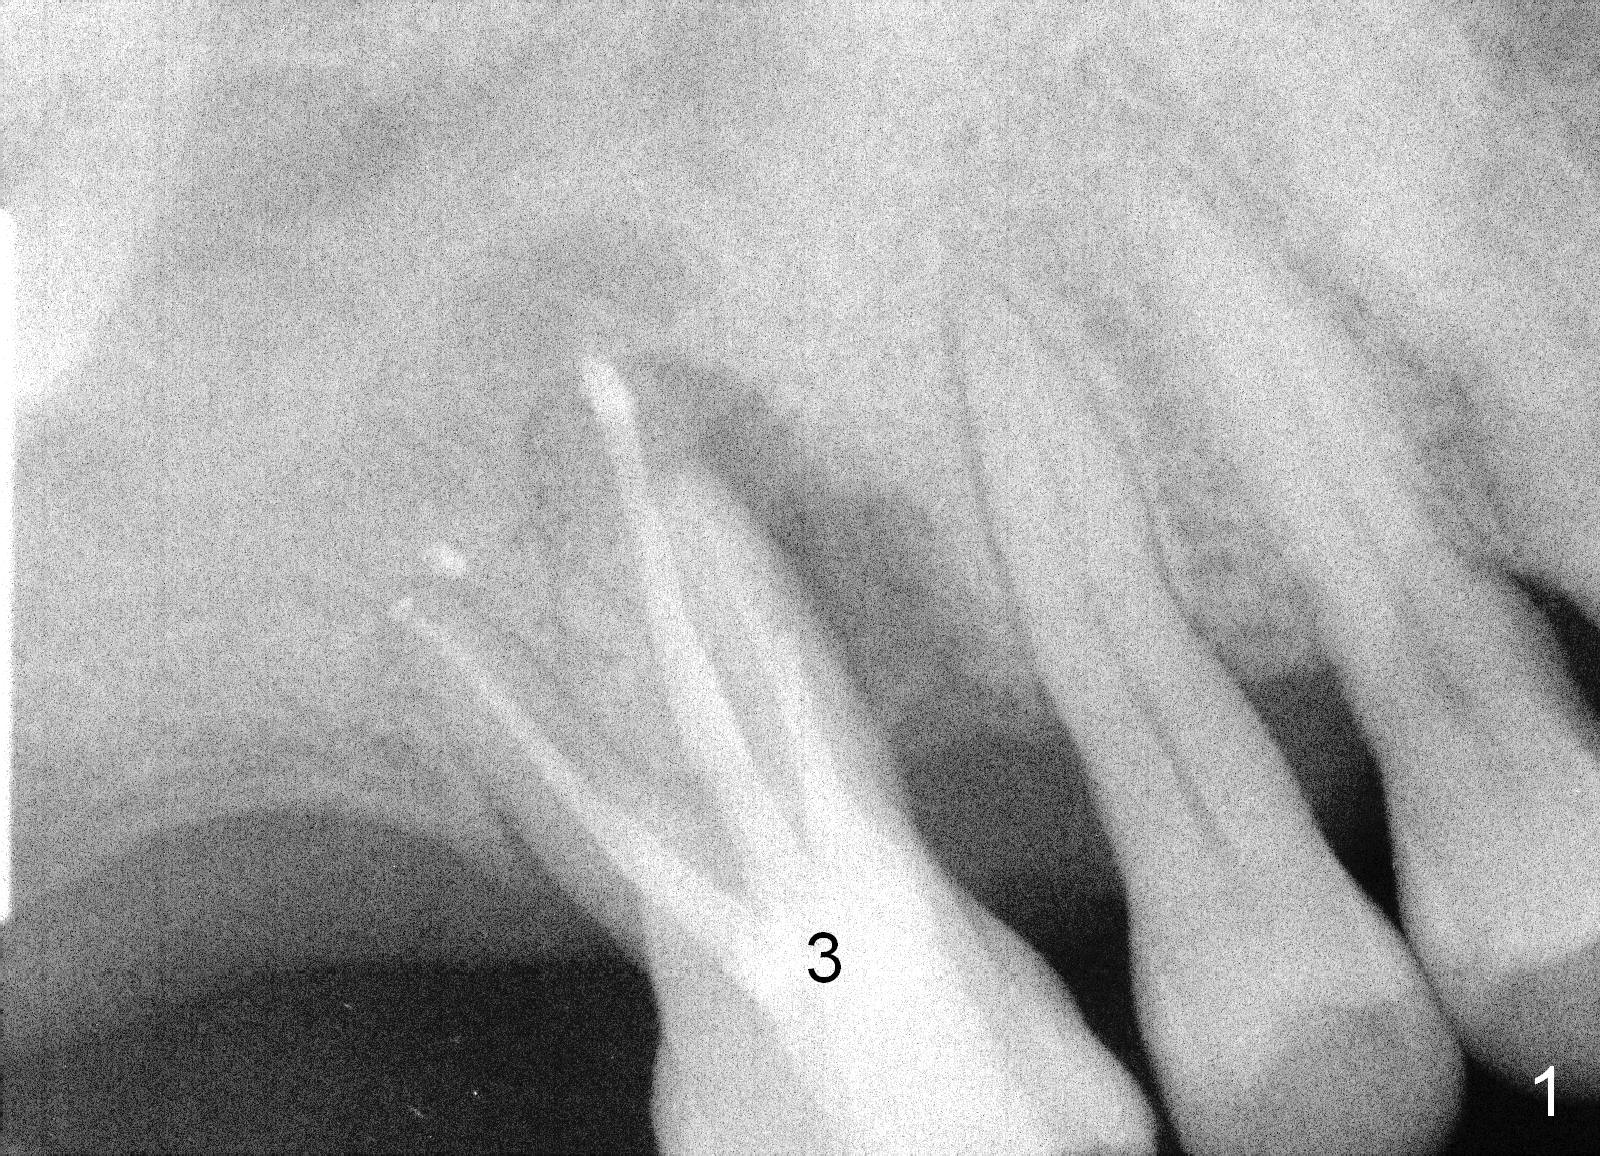

Two years post RCT, there is radiolucency around the MB root of the tooth #3 (Fig.1,2). Eleven days later, there is acute infection associated with MB and DB root fracture (Fig.3). According to the X-ray taken 11 days earlier (Fig.1,4), a long tissue-level implant (6x17 mm) is suitable for the site. In accordance with CBCT (coronal (Fig.5) and sagittal (Fig.6) sections) taken prior to RCT, a short bone-level implant (6.9x10 mm) is a more reasonable choice.

After extraction, the socket will be studied to determine where the bone is and where bony defects are for the site of the initial osteotomy. Start with 2 mm pilot drill or RT2, apparently ~ 6 mm depth, followed by reamers 2.5-3.5 mm and Tatum taps 4.5-7x17 mm (14 mm depth from gingival margin). Use a latch adapt with the torque wrench. Due to severe bone loss, the tap should not be too large (6 mm). If insertion torque is high and bone morphology is favorable, change to DIO taps and take necessary PAs to decide the length of the implant relative to the sinus floor and trajectory. If the depth is 10 mm or less, use SM; 12 mm UF. Based upon the most recent X-ray (Fig.3 with large lesion), the implant should be large and long (Fig.7: 7x17 mm).